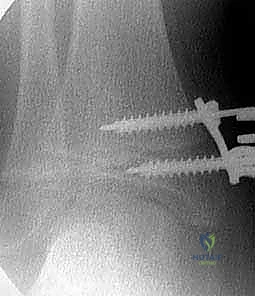

شكل 1 • أ. يعاني هذا الصبي البالغ من العمر 13 عاماً من السمنة والركبة الروحاء مجهولة السبب مع زيادة المسافة بين الكاحلين وعدم استقرار الرضفة. بدون تدخل جراحي دقيق لإعادة تنظيم الطرف، فإن التاريخ الطبيعي يشير إلى تدهور حتمي في وظيفة الركبة.

من الاكتشافات الشائعة التي يعالجها الدكتور هطيف بحرفية عالية هي عدم استقرار الرضفة (صابونة الركبة). الانحراف الميكانيكي للساق يؤدي إلى ارتخاء ثانوي في الأربطة، مما يجعل الصابونة عرضة للخلع الجزئي. الجميل في تقنية "النمو الموجه" أنها لا تصحح العظم فحسب، بل تحسن بشكل غير مباشر من استقرار الرضفة ومسار حركتها.

- تثبيت الصفيحة (Eight-Plate): يتم وضع شريحة معدنية صغيرة جداً (تشبه رقم 8) بحيث يكون منتصفها فوق صفيحة النمو مباشرة.

- إدخال المسامير: يتم إدخال مسمار في النصف العلوي من الشريحة (في المشاشة - Epiphysis) ومسمار آخر في النصف السفلي (في الكردوس - Metaphysis). هذه المسامير تعمل كمفصلة (Hinge) تسمح بنمو العظم في الجانب الآخر بينما تقيد النمو في هذا الجانب.